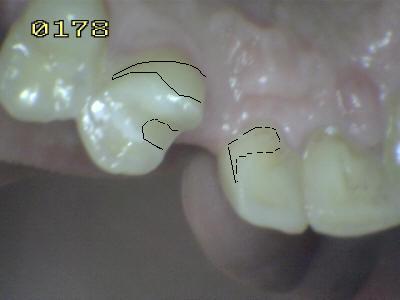

El tallado de un puente Maryland es

similar al tallado para una prótesis parcial removible; e incluso mas

sencilla porque solo hay dos piezas dentales pilares, adyacente a la

brecha edéntula, la cual es una sola pieza faltante. Y debe tener un

solo eje de inserción (ver imagen derecha), para esto hay que tallar los

planos guía y los apoyos oclusales. |

| El resultado de este extenso desgaste

superficial, es para que el retenedor del puente Maryland logre la mayor

estabilidad y retención, para que el metal tenga un solo eje de

inserción para el cementado. Como verá en el diagrama inferior el metal

no se extiende hasta el ángulo vestíbulo mesial, sino que queda un

milímetro escondido. Luego la porcelana del póntico suele cubrir este

ángulo. |